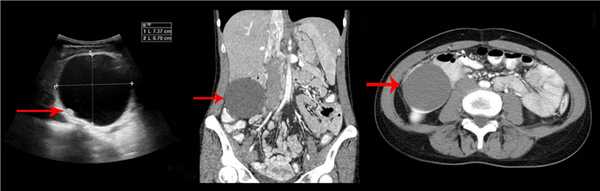

Рисунок. У новорожденного на УЗИ почек определяется гидронефроз (1) и расширенный мочеточник (2) справа. В мочевом пузыре двустороннее уретероцеле (3). При исследовании левой почки структурных изменений не выявлено.

Рисунок. На УЗИ определяется удвоенная чашечно-лоханочная система, расширена лоханка верхнего сегмента (1) и мочеточник на всем протяжение (2, 3), в мочевом пузыре уретроцеле (4). Полное или неполное удвоение чашечно-лоханочной системы возможно увидеть с помощью КТ-урографии.

Рисунок. КТ-урография (1) показывает неполное удвоение ЧЛС слева: два мочеточника соединяются на входе в таз и единым мочеточником вступают в мочевой пузырь; внутрипузырная часть мочеточника расширена (красная стрелка) — уретероцеле. Уретероцеле хорошо видно на рентгенограммах (2) при экскреторной урографии: правый мочеточник расширен на всем протяжении, дистальный отдел кистозно расширен — «голова кобры».

Рисунок. Уретероцеле (стрелка) на УЗИ и КТ.

Рисунок. Дистальный отдел мочеточника расширен, в мочевом пузыре анэхогенное образование с тонким и ровным контуром — уретероцеле.